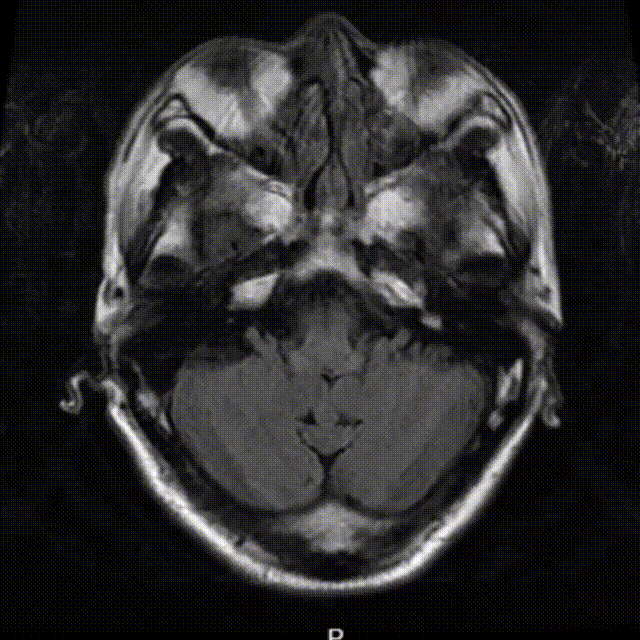

头部MRI+DWI提示:左侧大脑半球多发脑梗死,DWI像与T2 FLAIR像不匹配。